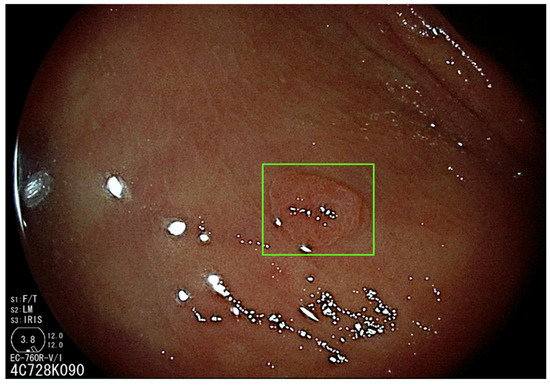

3.1. Artificial Intelligence-Assisted Detection (CADe)